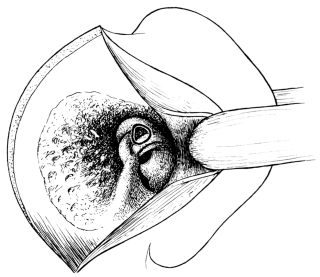

| ENUCLEATION OF THE GLOBE AND ALLIED OPERATIONS | |

| Enucleation, 255. Evisceration, 257. Mules’s Operation, 259. Frost’s Operation, 259. Operations upon the Socket after Removal of the Eye—Paraffin Injection, 260. Operations for Restoration of a Contracted Socket—Skin-grafting, 261; Inclusion of Flaps (Maxwell’s Operation), 261 | 255–262 |